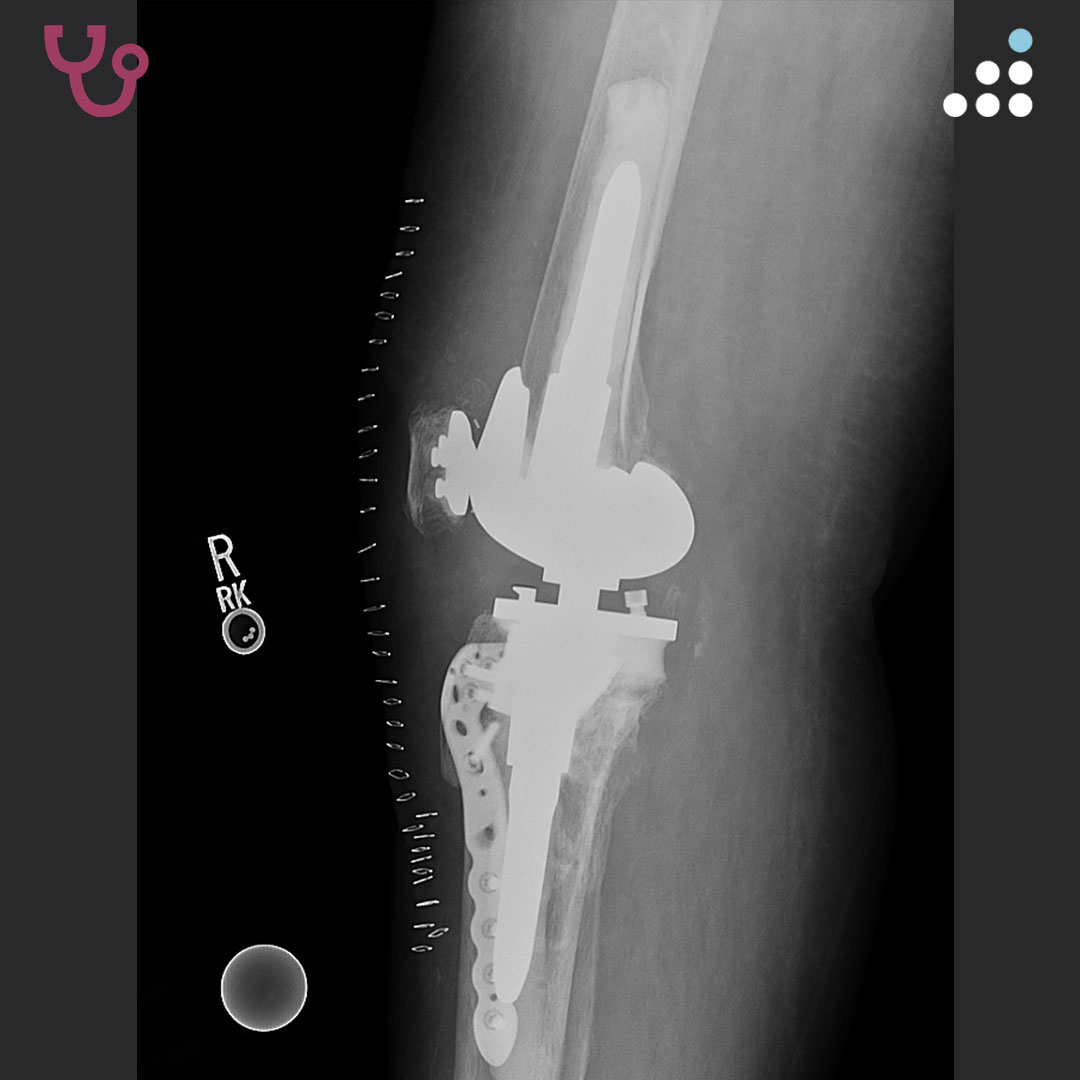

@orthobullets @HSpecialSurgery @bonesmith_ @PeltMD @BennerKneeMD @EdinburghKnee @generalorthomd @yoon_rs @DrFraneNicholas @stevemchale @FractureDoc Always tough cases but really like the choices here. I think an important point is the metaphysical fixation. This can help recreate the joint line when cortical bone is defeicient

Nice job Dr Cyndi Kahlenberg